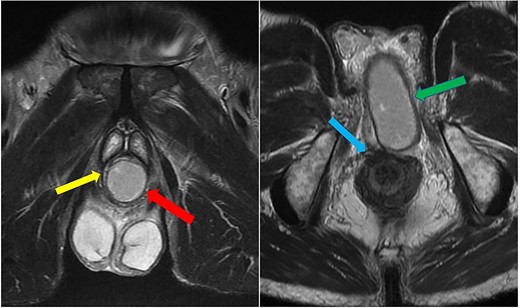

He was put on an empirical course of ciprofloxacin to treat a presumed complicated UTI, and a pelvic MRI was requested. Urine culture grew an Enterobacter cloacae organism. The MRI scan revealed a 7 × 3 cm perineal collection inferior to the prostate and adjacent to the membranous urethra, with increased wall enhancement and fluid with restricted diffusion, with a diagnosis of Cowper’s syringocele (Fig. 3).

Case 2: T2-weighted sagittal MRI image demonstrating a complex, cystic perineal collection (blue arrow), seen in relation to one of the corpus cavernosa (yellow arrow).

The patient was reviewed again a week later. On examination, a tender perineal mass extending into his posterior scrotum had developed. Again, there were no perianal skin abnormalities on examination. He was put on intravenous antibiotics, and a repeat MRI of his pelvis was organized. This revealed a persistent perineal collection, in proximity with, but not involving, the external anal sphincter, as well as the bulbar urethra and scrotum (Fig. 4).

Case 2: coronal and axial T2-weighted images demonstrating the collection (red and green arrows) significantly compressing the urethra and corpus spongiosum (yellow arrow) to the right of the midline, and close to, but not involving, the anal sphincter (blue arrow).